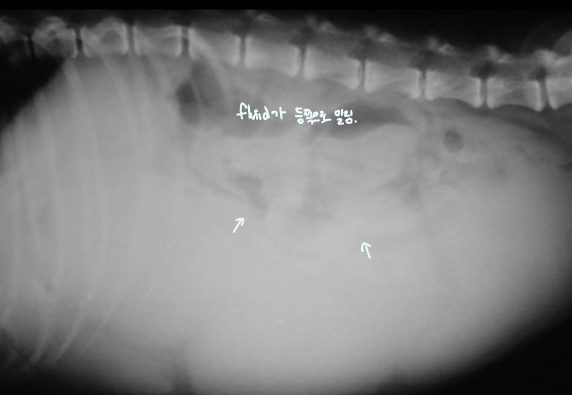

Serosal detail

- Serosal detail์ด ๋จ์ด์ง๋ฉด fluid๊ฐ ์ฐผ๋ค๋ ์๋ฏธ

- Transudate : ์ฐ์ฌ๋ถ์ , ๊ฐ๋ถ์ , hypoalbuminemia/proteinemia^[์กฐ์ง ์ผํฌ์์ด ๊ฐ์ํ๋ฉด์ ๋น ์ ธ๋์ฌ ์ ์์]

- Pus : peritonitis โ trauma, pancreas

- Blood : ๊ต์(ํํ์ฅ๊ธฐ์ ํ์ด), neoplasia, HBC

- Urine : pelvic fx๋ฅผ ๋๋ฐํ HBC

- = Thumb printing sign :๋ณต์๊ฐ ์ฐจ์ ๊ฒ์์(gas), ํฐ์(fluid)๋ก๋ง ๊ตฌ๋ถ๋จ.